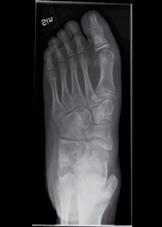

Figur 2a och b. Patient med valgusbelastad fot och hallux valgus interfalangeus Postoperativ bild där calcaneus förlängts så att framfotsabduktionen försvåras. Stortån har åtgärdats genom en kilosteotomi på grundfalangen.

och övriga framfoten glider på det rundade talushuvudet varvid mediala ligamentapparaten successivt blir alltmer uttänjd (fig 1) samtidigt som peroneusmuskulaturen bidrar till abduktionsställningen. Vanligen står inte hälarna inte så kraftigt i valgus inledningsvis, men detta kommer ofta med tiden. I och med att framfoten vid belastning pekar mer lateralt minskar plantarflexorernas möjlighet att hålla emot underbenets strävan framåt över foten, och risken för knäande gång ökar därvid ytterligare. Speciellt hos barn med sämre gångförmåga tillkommer med tiden också ofta en utåttorsion av underbenen och ibland även en valgusställning i själva talocruralleden. En idag vanlig operationsmetod, för att på barn med måttlig framfotsabduktion motverka naviculares lateralglidning på talus, är en förlängningsosteotomi på calcaneus 1-2 cm bakom calcaneocuboidleden. Efter att osteotomispalten bänts isär införes en kil av trikortikalt cristaben eller annat strukturellt bengraft (fig 1c, 2b). Är detta otillräckligt (som t.ex. vid samtidig ledlaxitet) kan foten stabiliseras ytterligare genom talonaviculär artrodes. För de mest felställda och rigida fötterna kan trippelartrodes bli aktuell.

Stortåproblem är vanliga hos de lite äldre barn som fortsätter att gå med tåisättning av foten. Vanligen är felställningen störst på MTP-nivå (fig 1a), men ibland består den huvudsakliga prolemet av en hallux valgus interfalangeus med clavusbildning motsvarande IP-leden (fig 2a). För att nå bestående resultat av hallux valgusingrepp kan det vara klokt att överväga MTP I artrodes (fig 1d) eftersom felställningen annars tenderar att återkomma om barnet fortsätter att gå med tåisättning.